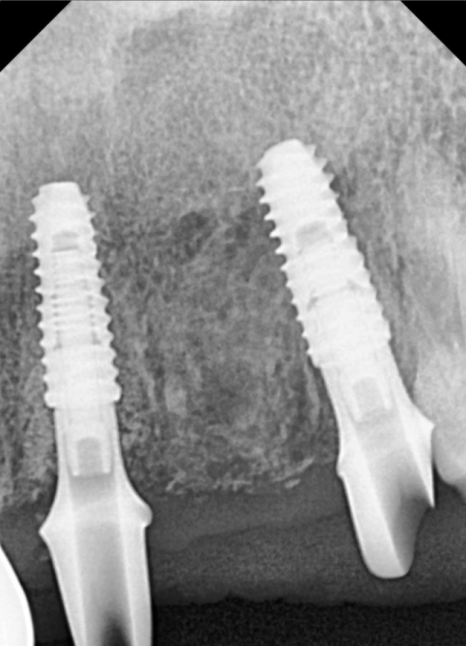

앞니 임플란트는

단순히 튼튼하게 심는 것을 넘어

'옆 치아와 얼마나 자연스럽게 어울리는가'가

생명입니다.

특히 이 환자분처럼 주변 치아도 크라운인 경우,

색상이나 각도가 조금만 어긋나도

매우 어색한 인상을 줄 수 있는데요~

어떠세요? 주변 치아와 조화를 이루며

아주 자연스럽게 마무리된 모습이죠?

단순히 심는 것에 그치지 않고

뼈 상태, 잇몸 회복,그리고 정교한 교합까지

세밀하게 고려하여 자연스러운 보철이

완성되었습니다.^^